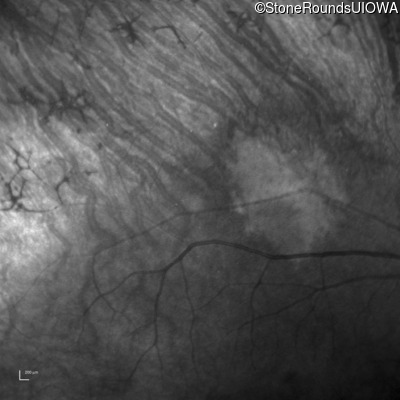

Infrared Fundus Photograph - Right - 20/32

Exemplar